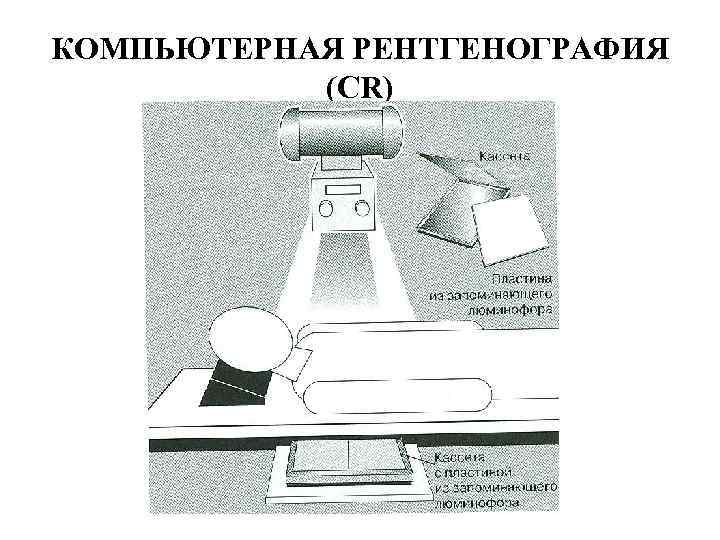

КОМПЬЮТЕРНАЯ РЕНТГЕНОГРАФИЯ (CR)

КОМПЬЮТЕРНАЯ РЕНТГЕНОГРАФИЯ (CR)

СЧИТЫВАЮЩЕЕ УСТРОЙСТВО И КОМПЬЮТЕРНАЯ РАБОЧАЯ СТАНЦИЯ

СЧИТЫВАЮЩЕЕ УСТРОЙСТВО И КОМПЬЮТЕРНАЯ РАБОЧАЯ СТАНЦИЯ

ЦИФРОВЫЕ ТЕХНОЛОГИИ ПОЛУЧЕНИЯ РЕНТГЕНОВСКОГО ИЗОБРАЖЕНИЯ Методы компьютерной визуализации развиваются быстро, поэтому терминология полностью не разработана. Но некоторые термины уже приняты. PACS – Picture Archiving and Communication System Компьютерная система архивирования и передачи цифровых изображения состоит из аппаратной части (компьютеры, объединенные в локальную сеть и блок хранения информации) и программного обеспечения, связывающего в единую сеть различные диагностические установки.

ЦИФРОВЫЕ ТЕХНОЛОГИИ ПОЛУЧЕНИЯ РЕНТГЕНОВСКОГО ИЗОБРАЖЕНИЯ Методы компьютерной визуализации развиваются быстро, поэтому терминология полностью не разработана. Но некоторые термины уже приняты. PACS – Picture Archiving and Communication System Компьютерная система архивирования и передачи цифровых изображения состоит из аппаратной части (компьютеры, объединенные в локальную сеть и блок хранения информации) и программного обеспечения, связывающего в единую сеть различные диагностические установки.